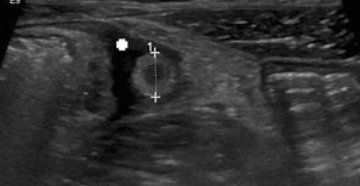

MEJOR MÉTODO DX NIÑOS

USG MAYOR 6 MM

EN DEDO DE GUANTE O SIGNO DE DIANA

DEDO EN GUANTE

Diana